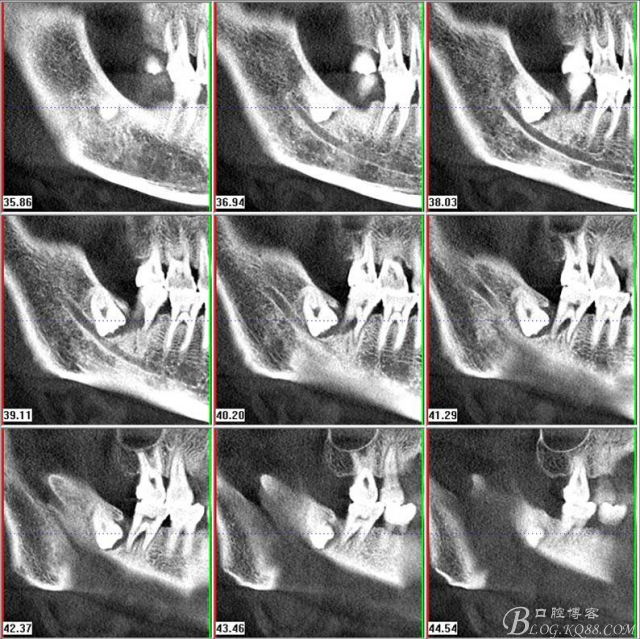

二、術(shù)前CBCT影像:

圖3.通過(guò)矢狀面和冠狀面來(lái)判斷48與下頜管及47的關(guān)系